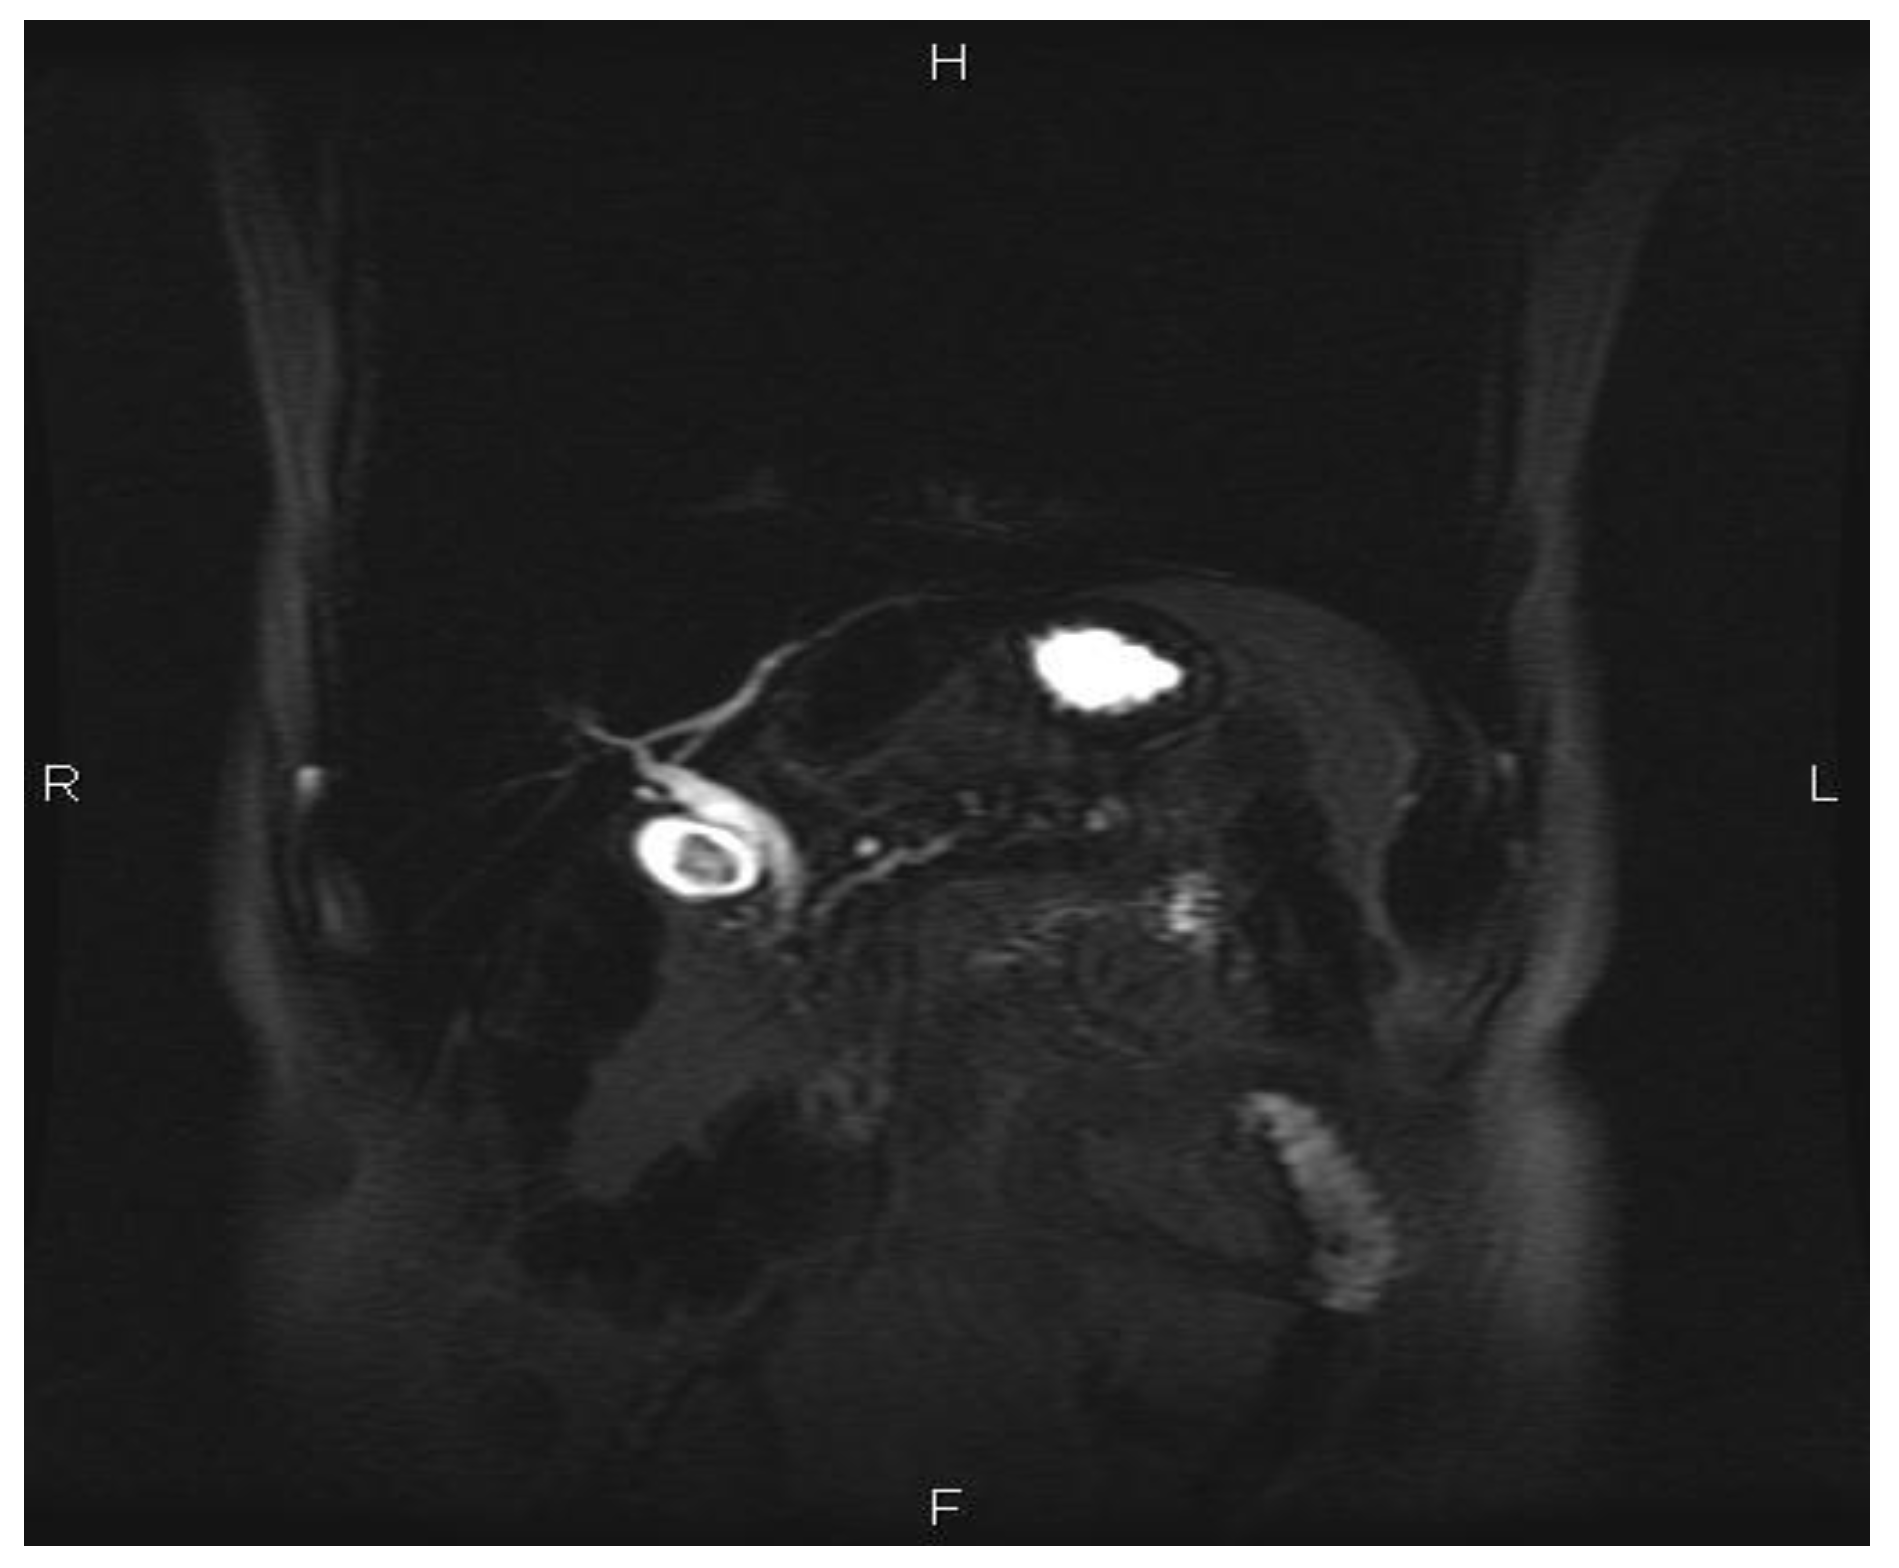

A 52-year old Caucasian man was diagnosed with chronic recurrent pancreatitis in 2007. The diagnosis was based on personal pathological history (repeated episodes of acute pancreatitis, biochemical, and imagistic investigations). A suggestive aspect of chronic pancreatitis evidenced by cholangio nuclear magnetic resonance is shown in Figure 1, Figure 2, Figure 3.

Figure 2. Coronal T2 single shot long TE section: irregular Wirsung duct dilatation associated with small peripheral canal dilations.